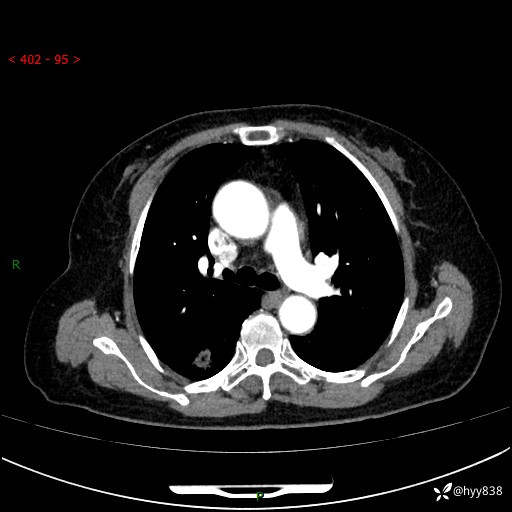

71岁/女,发现肺结节1月。偶然发现孤立肺结节,邻近叶间裂凹陷---结果公布(再回首)

【患者信息】:71岁/女

【主诉】:发现肺结节1月

【现病史及既往史】:2024年9月患者因“胆囊结石”于我院肝胆外科住院,期间完善胸部CT提示:右下肺结节灶,高危结节?感染?,病程中无畏寒发热,无咳嗽、咳痰,无活动后气短,无心慌胸闷,无胸痛、咯血,无头晕头痛,无腹痛腹泻,无四肢肌肉酸痛等不适,当时建议其择期复查。今日患者为求进一步复查就诊于我院,完善胸部CT提示:右肺结节,较前一致,遂门诊“肺部结节”收入我科。 自本次起病以来,患者精神、饮食、睡眠可,大小便正常,体力、体重未见明显异常。

【检查】:胸部CT平扫+增强